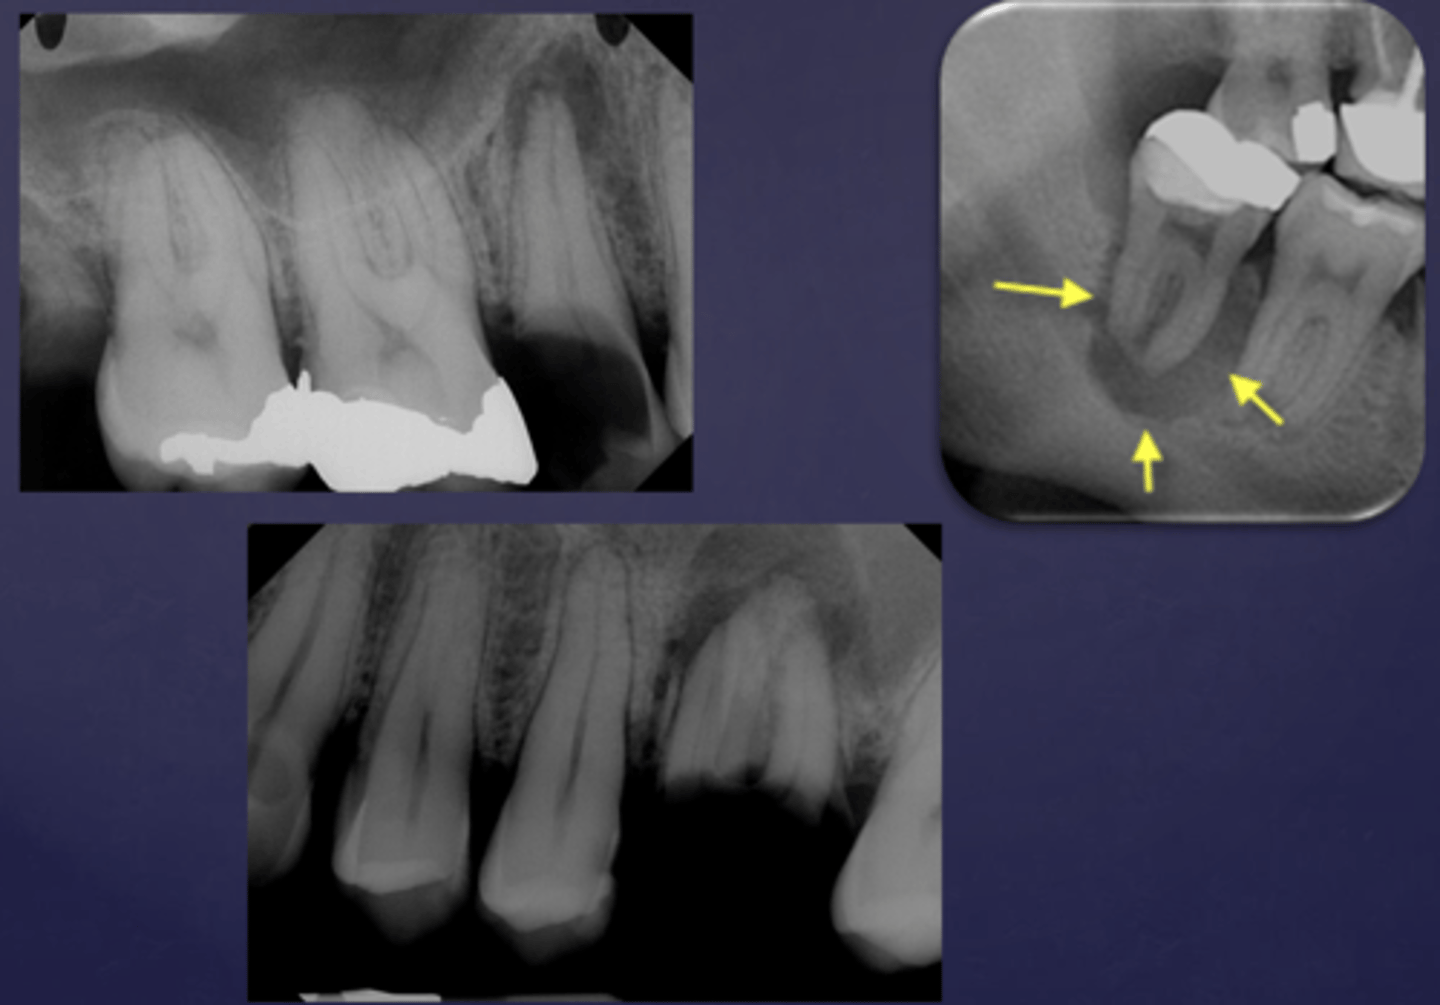

Well defined or poorly defined?

well defined

poorly defined

The arrows are pointing at the loss of apical lamina dura and periapical radiolucency, what is the differential diagnosis?

apical rarefying osteitis

What is the differential diagnosis?

healthy (no loss of lamina dura, submandibular gland fossa- normal anatomy)